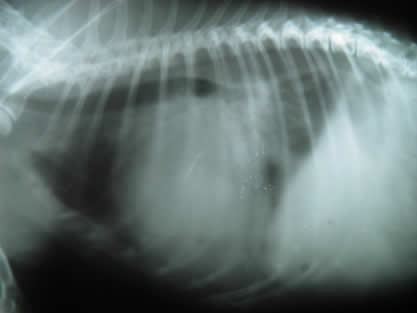

• Radiografías de tórax para observar los pulmones, la forma y tamaño del corazón.

En nuestra clínica contamos con equipos diagnósticos adecuados para abordar y diagnosticar estas enfermedades, por ejemplo electrocardiograma, rayos x, ultrasonido y una preparación constante en esta área. Además tenemos un servicio anexo de cardiología para abordar enfermedades complejas y que necesitan equipos de diagnostico y conocimientos mas especializados.

Rayos en mascotas Rayos en mascotas